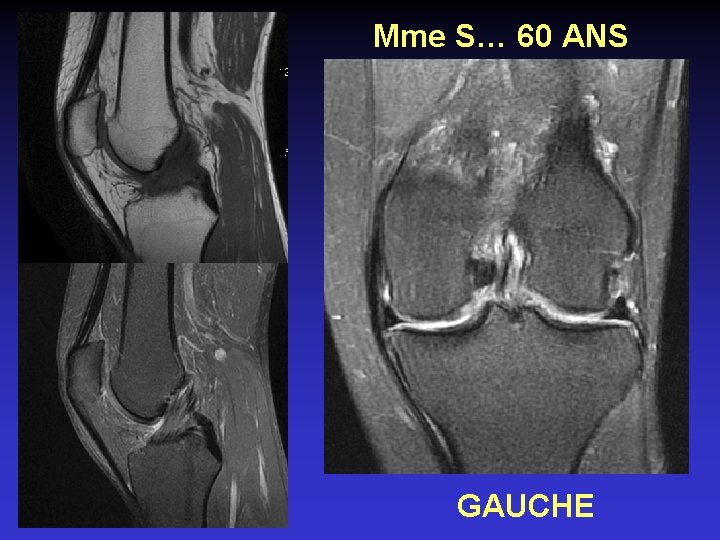

ATTEINTE BILATERALE • Non exceptionnelle • Concomitante ou décalée dans le temps

Mme S… 60 ANS DROIT

Mme S… 60 ANS GAUCHE